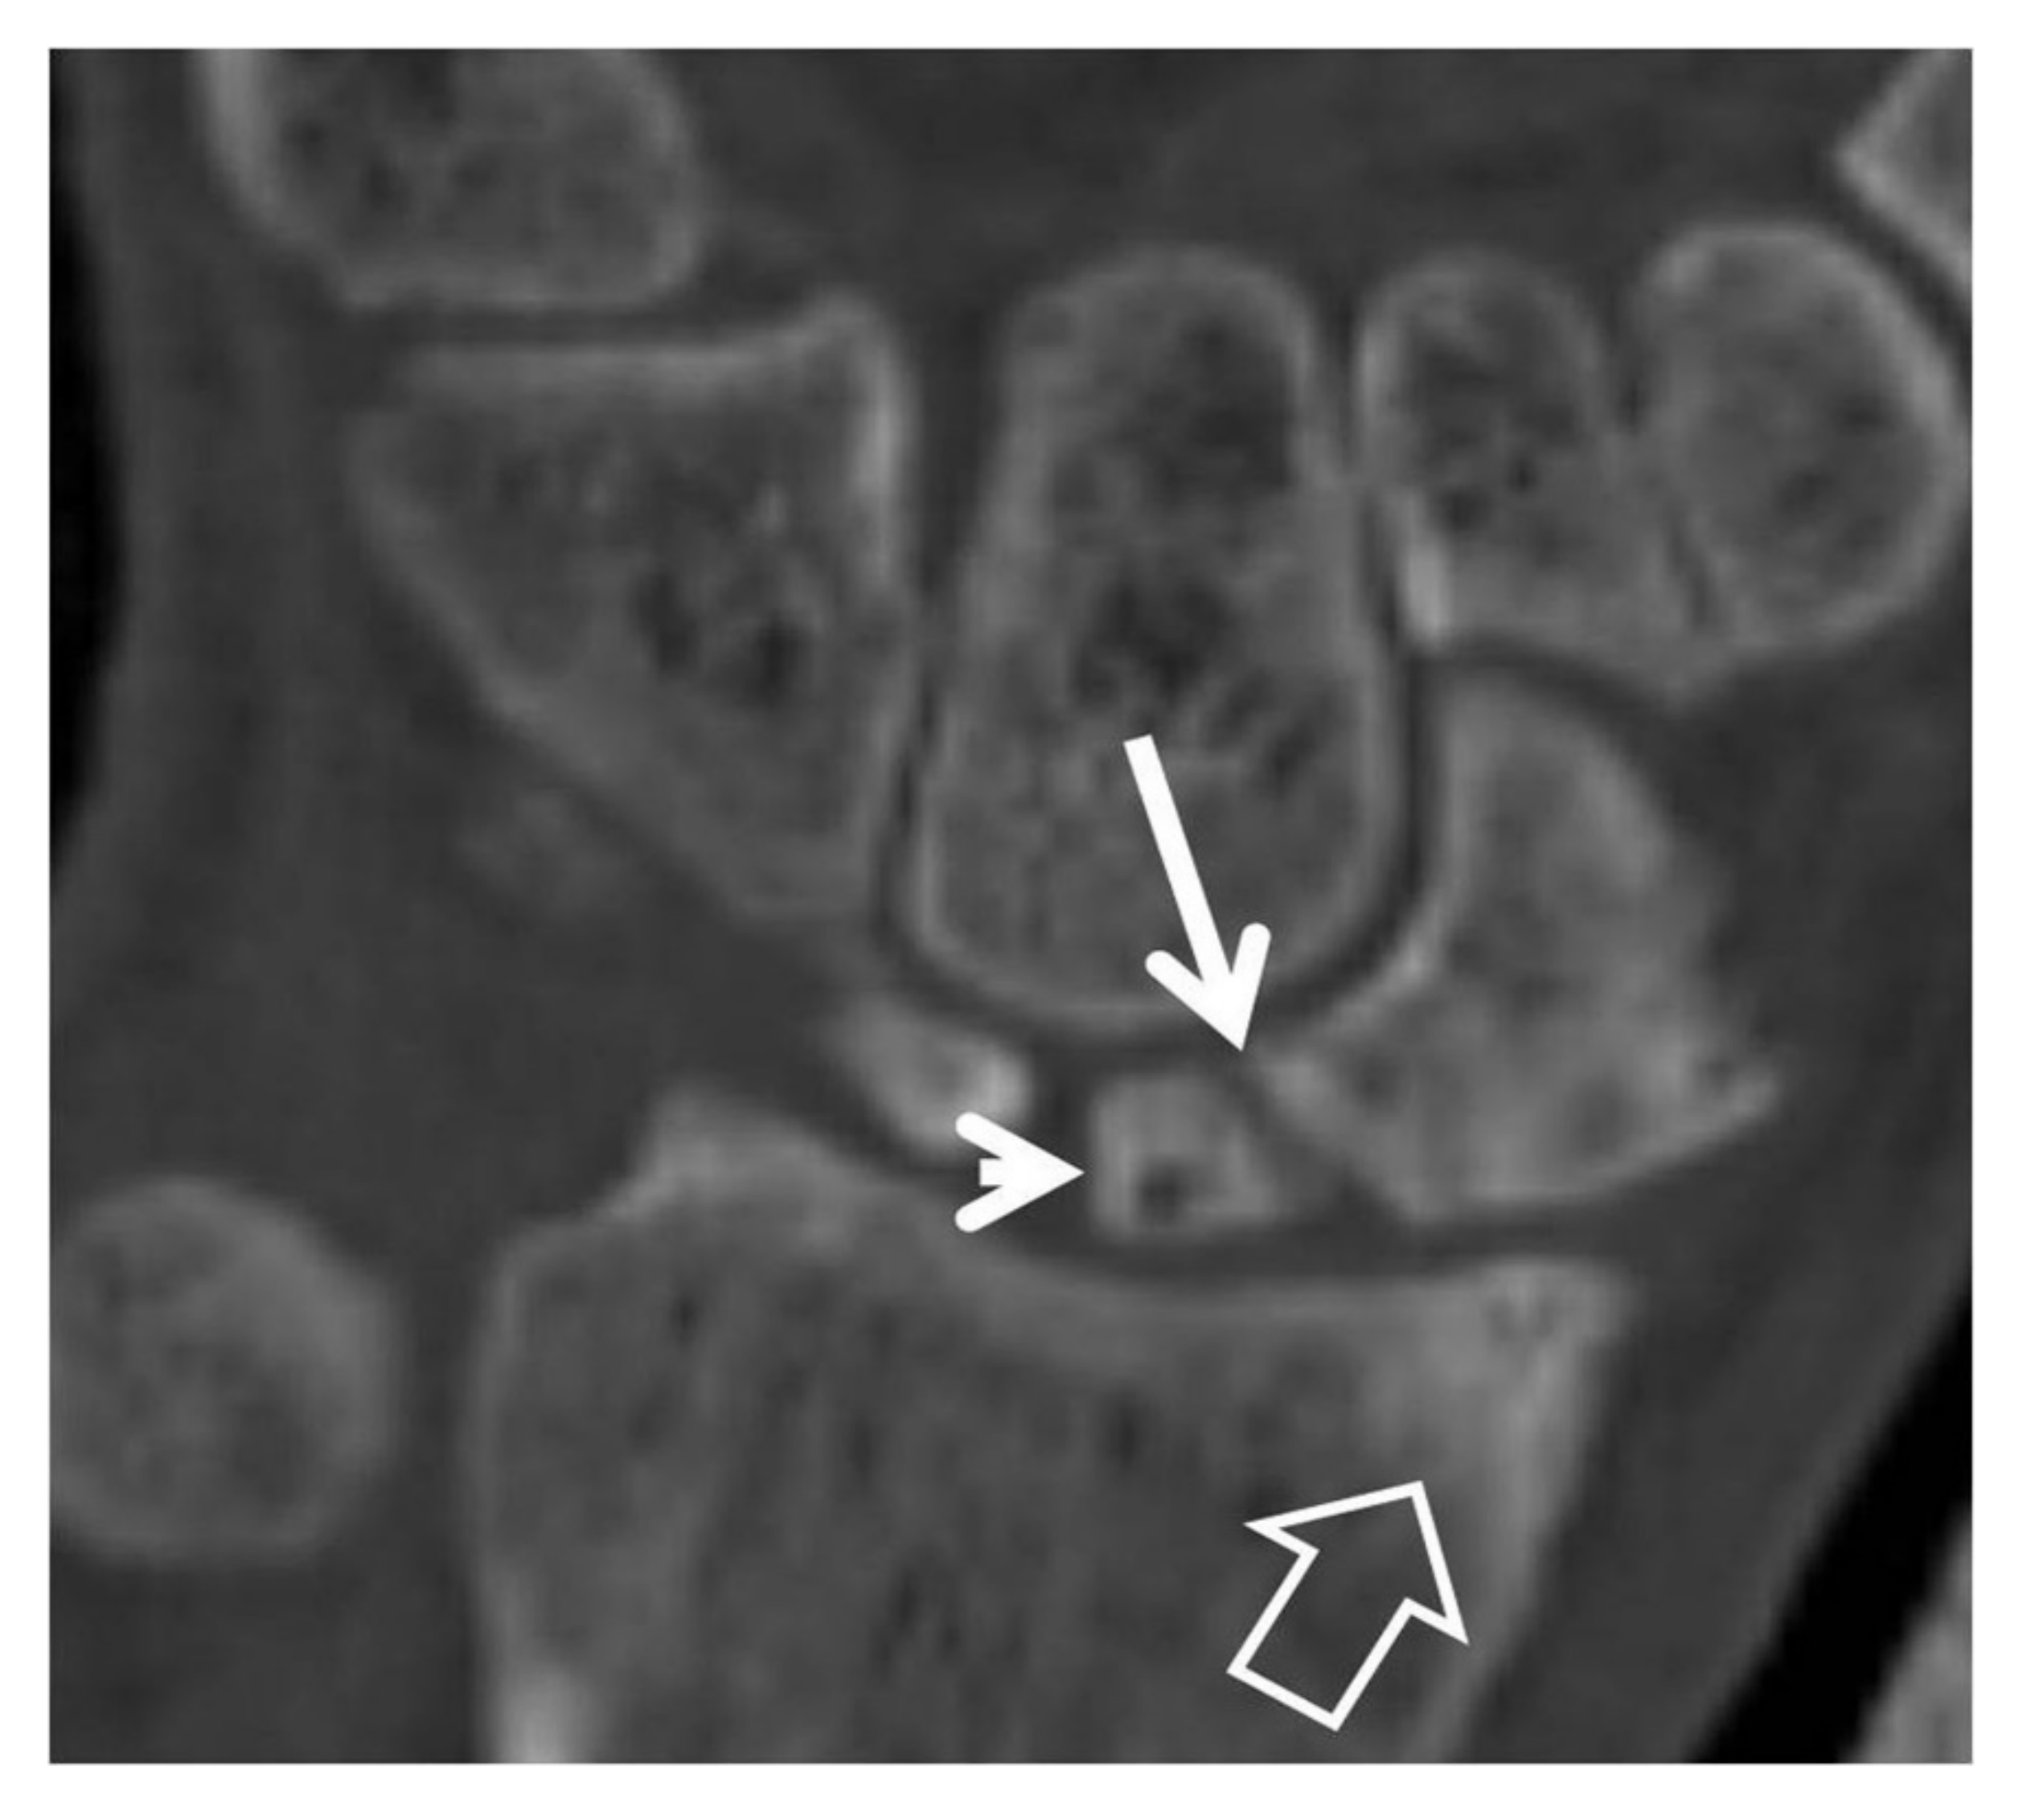

CT-arthrography (CTa) is performed with an iodine contrast material injected in specific wrist joints. For depicting a SLL tear, a single injection at the radioscaphoid joint is performed in our department under fluoroscopic or ultrasound guidance. In the presence of a tear, the midcarpal joints will be opacified (Figure 8).

Figure 8.

A 33-year-old with a history of scaphoid fracture. (A) Coronal CT-arthrographic image showing the scaphoid pseudarthrosis (open arrow), a radial styloid process fracture (arrowhead) and an intact scapholunate ligament (arrow). (B) Axial CT-arthrographic image showing the intact dorsal (arrow) and palmar (open arrow) parts of the scapholunate ligament. A 56-year-old male patient who was involved in a motor vehicle accident 1 year prior to current imaging. Coronal (C) and axial (D) CT-arthrographic images showing a tear at the membranous (arrow) and palmar (open arrow) parts of the scapholunate ligament.

In SNAC, one of the main MDCT findings is the exact location of the non-union scaphoid fracture (Figure 5b, Figure 6a, Figure 7 and Figure 9). This location is important for the prognosis of the disease as a non-union fracture at the proximal third of the scaphoid has a higher chance of dorsal flexion of the lunate and is thus more prone to extensive cartilage degeneration.

Figure 9.

A 42-year-old male patient with pseudarthrosis following previous scaphoid fracture. Coronal CT reconstruction showing the fracture non-union (arrow), the proximal pole osteosclerosis with cyst formation (arrowhead) and the subarticular osteosclerosis of the radial styloid (open arrow) in keeping with early osteoarthritis.